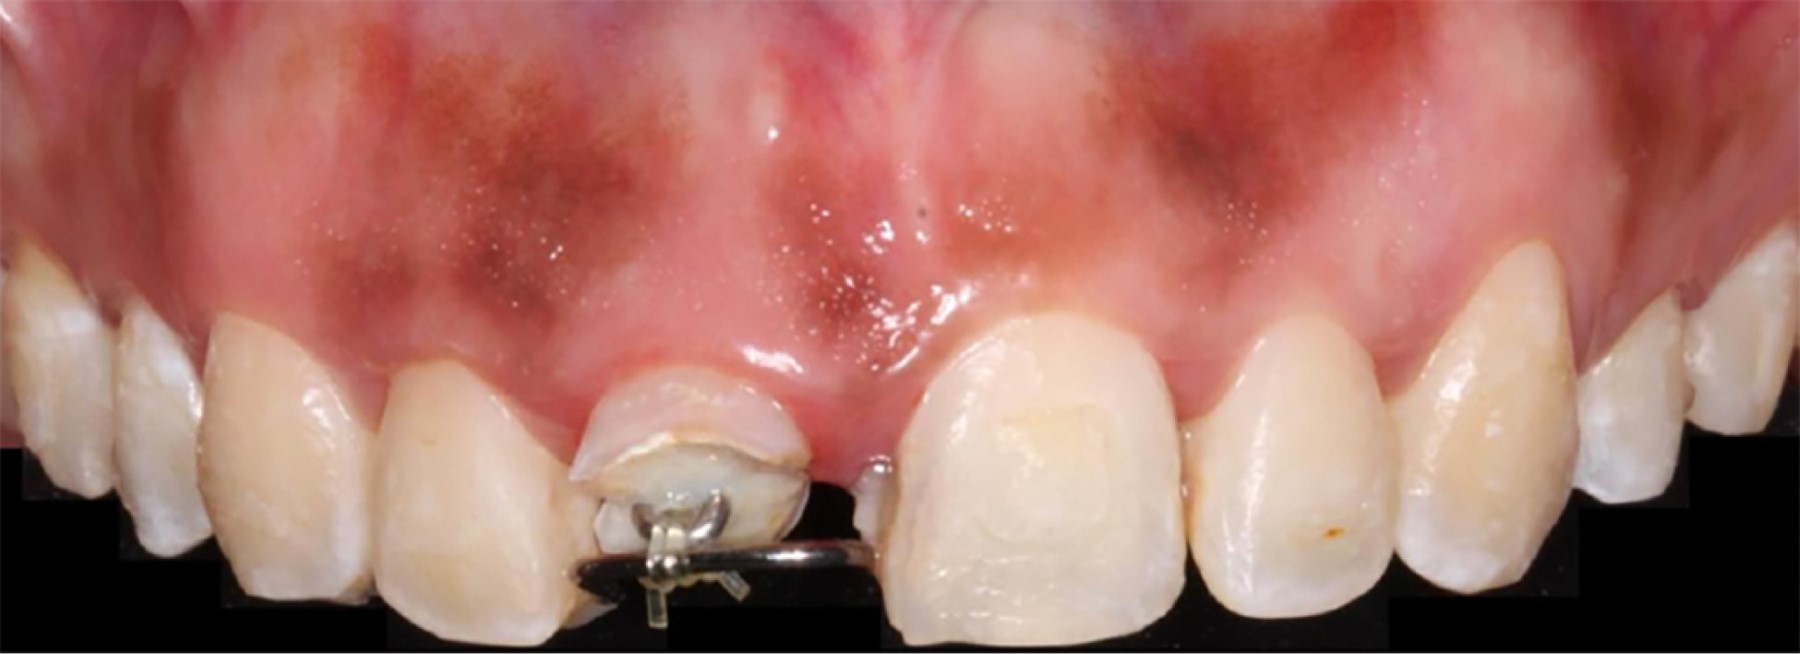

Una vez concluido este proceso, se realizó el cambio de cadenas elastoméricas de segunda generación con un periodo semanal. Al cumplir la tercera semana, se observó el contacto del loop con el alambre de ortodoncia, cumpliendo con el objetivo de los 3 mm de extrusión necesarios (Figura 3). Se tomó una radiografía de control donde se pudo constatar la migración en sentido coronal de dicho órgano dentario (Figura 4).

Figura 3